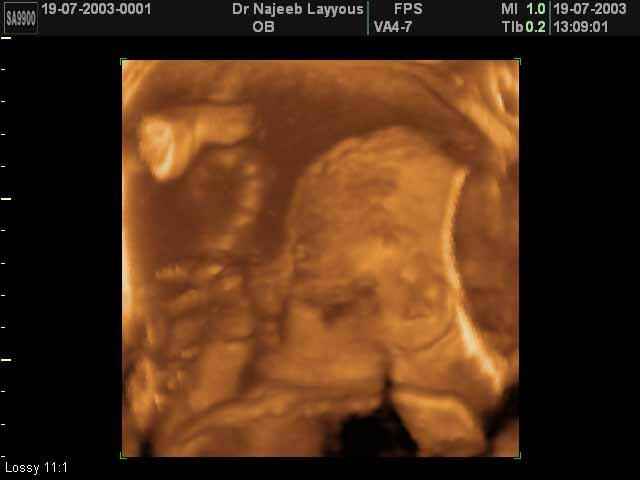

- 3D Fetal Profile Ultrasound Scan Photos

3D Fetal Profile Ultrasound Scan Photos | Dr N Layyous